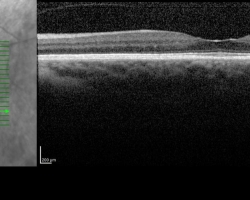

- OCT maculaire : montre l’œdème papillaire à droite mais l’objectif de l’examen est surtout d’éliminer une pathologie maculaire à l’origine de cette baisse d’acuité visuelle.

FO : cf. images jointes